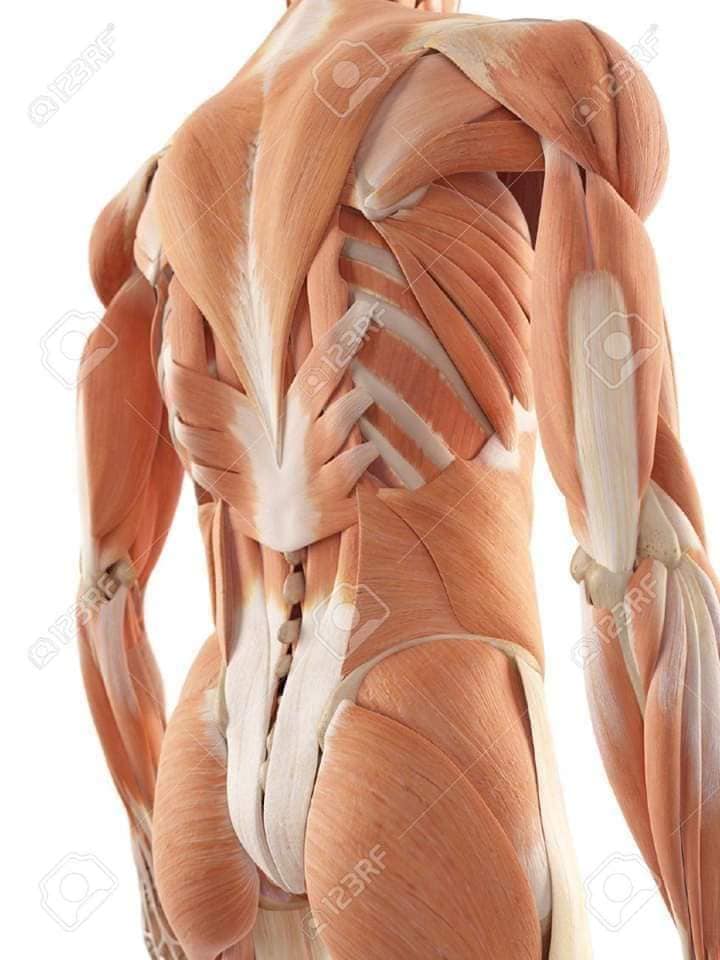

Спинні м'язи

Спинні м'язи виконують функції підтримки хребта, а також дозволяють здійснювати рухи тулуба.

Поверхневі спинні м'язи

М'язи, що піднімають лопатку: Трапецієподібний м'яз: великий м'яз, що покриває верхню частину спини. Його функція - підтримка і рух лопаток, а також забезпечення стабільності хребта.

М'язи, що ведуть лопатку до хребта: Широкий м'яз спини: великий м'яз, що розташований в нижній частині спини. Він відповідає за рухи плечей і лопаток, а також за розширення верхньої частини тулуба.

Глибинні спинні м'язи

М'язи, що забезпечують стабільність хребта: М'язи, що розташовані між хребцями: включають мускулатуру, яка забезпечує стабільність і підтримку хребта, а також дозволяє здійснювати рухи хребта.

М'язи, що здійснюють ротацію та нахили

М'язи, що забезпечують ротацію хребта: Ротаційні м'язи: допомагають у здійсненні обертальних рухів тулуба, а також у підтримці рівноваги і стабільності хребта.